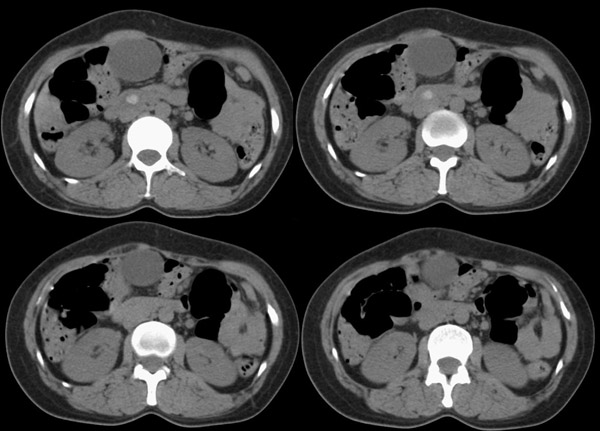

胆总管矢状及冠状重建:

行胆囊切除术及胆总管探查术:探查见肝脏大小正常,肝缘稍钝,肝表面光整,胆囊大小12*3*3cm3,壁水肿增厚约0。5cm,张力稍高,胆囊与大网膜呈纤维粘连;胆总管宽约2cm,壁明显增厚,触摸胆总管,隐约可触及一条状物,于胆总管做一长约1、5cm的纵行切口,用取石钳在胆总管内取出一条长约16cm长黑色的长条状物,较脆易折断,宽约0、6cm,证实为蛔虫尸体。用探子往下探,未发现下端结石最后诊断:胆道蛔虫症继发胆系梗阻性扩张。

疑惑:1、ct表现胆总管下端有结石影,但手术中未发现???

2、胆总管下端若是阳性结石,那么这条16*0、6cm2的大蛔虫是如何进入胆总管的?!

结合胆道蛔虫病史,蛔虫性胆系结石并胆系梗阻能明确诊断。至于说没有发现胆总管下端阳性结石,因为已经取出来了。